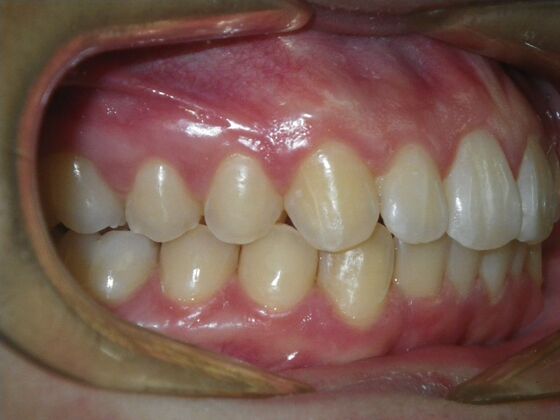

Patient presents with constricted upper and lower arches that will need expansion as well as slenderizing (IPR) to correct upper and lower anterior crowding.